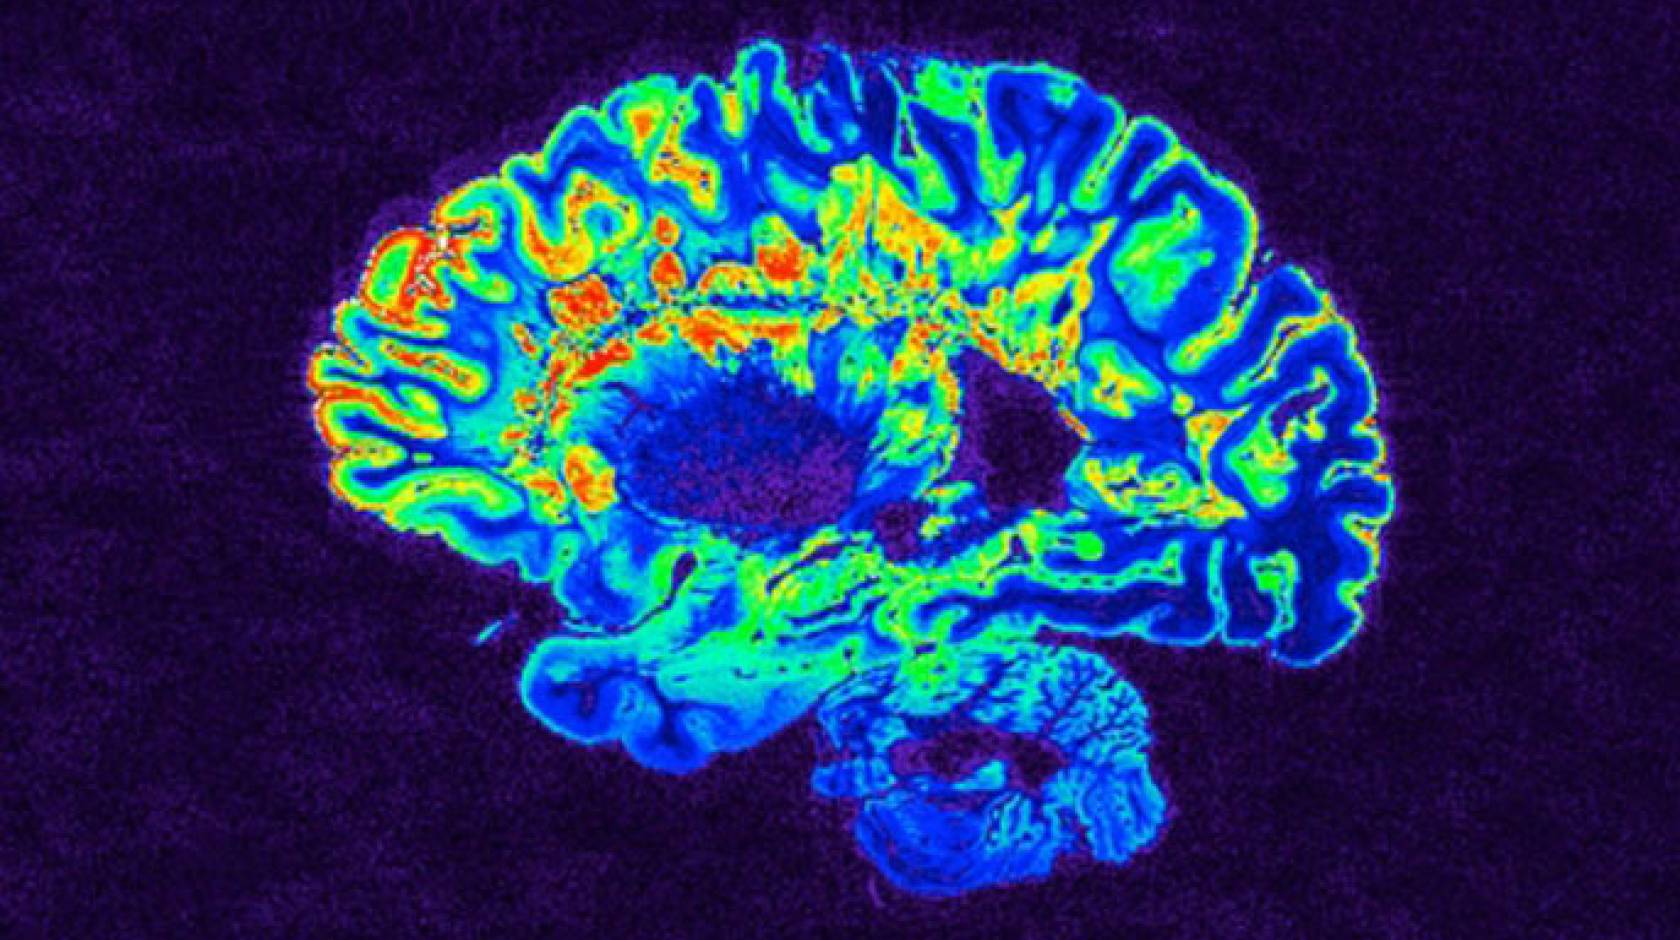

Although the research team could not directly observe evidence of rebuilding of myelin in trial participants using magnetic resonance imaging (MRI), Chan and Green said that this reflects a weakness of current MRI techniques as a tool for this purpose rather than evidence that myelin regeneration did not take place. “We still don’t have imaging methods that have been proven to be able to detect remyelination in humans,” said Chan.